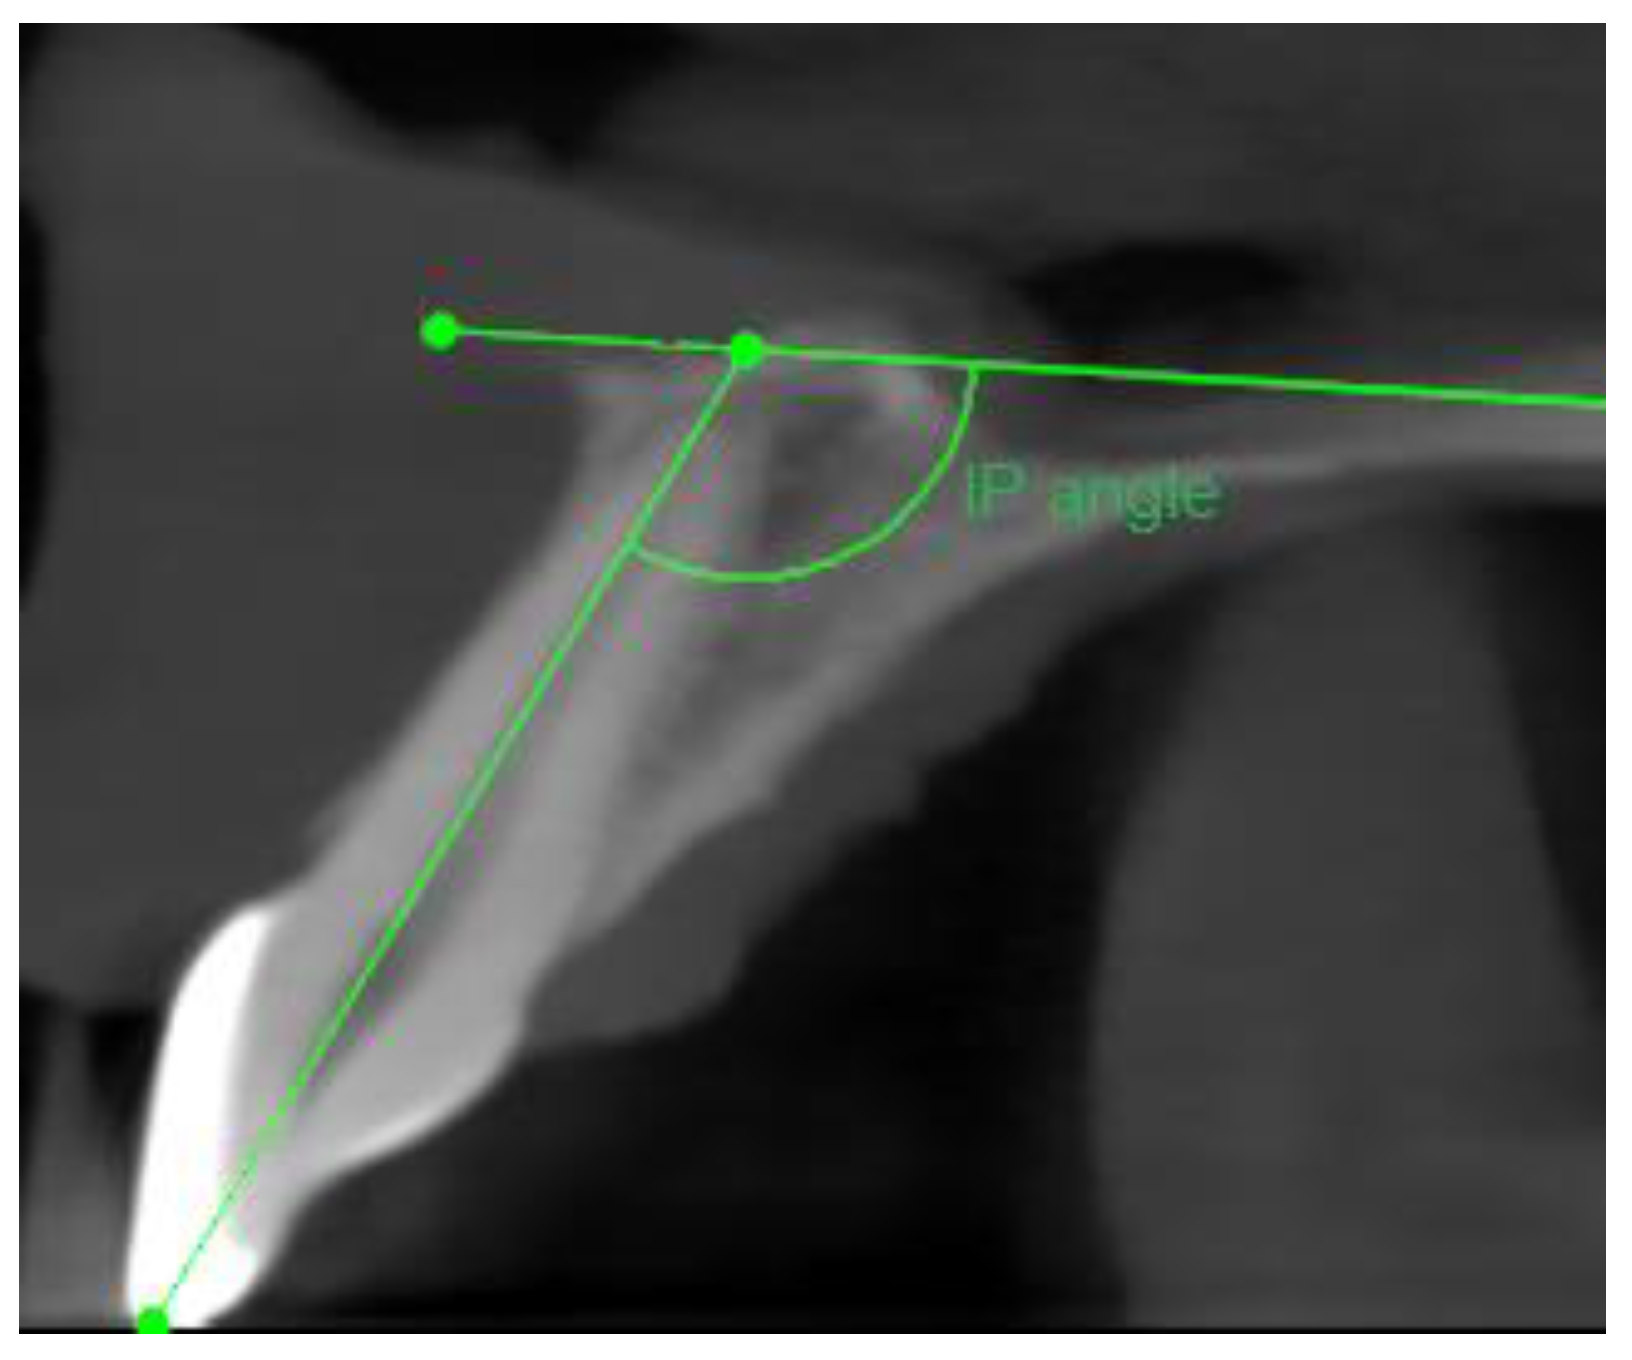

- Angle formed by the long axis of the incisive canal and the palatine plane—IP angle.